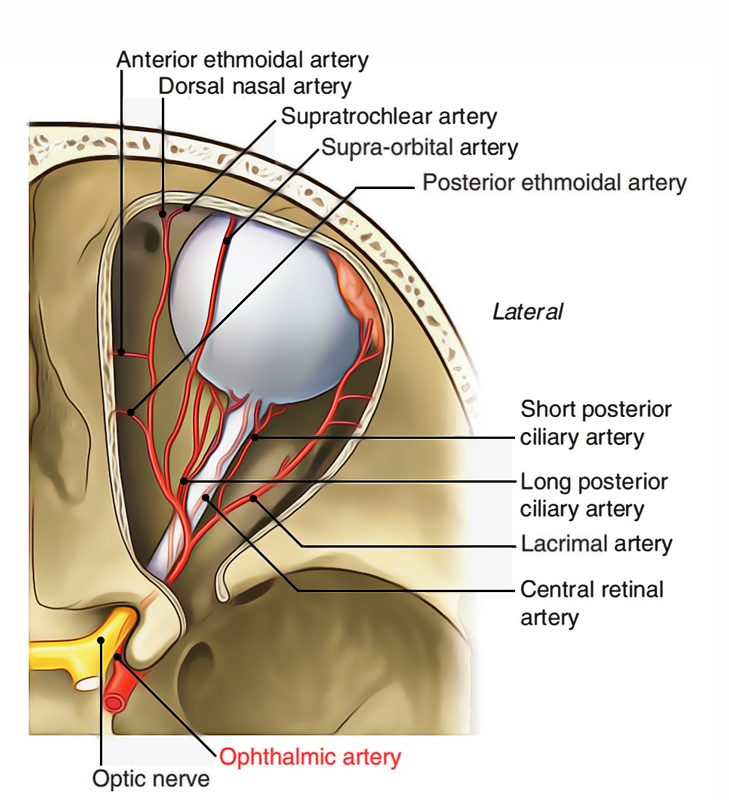

Ophthalmic a.

- Dorsal nasal a.

- Supratrochlear a.

- Ant./ Post. ethmoid a.

- Supraorbital a.

- Ciliary a.

- Lacrimal a.

Optic canal

- Ophthalmic a.